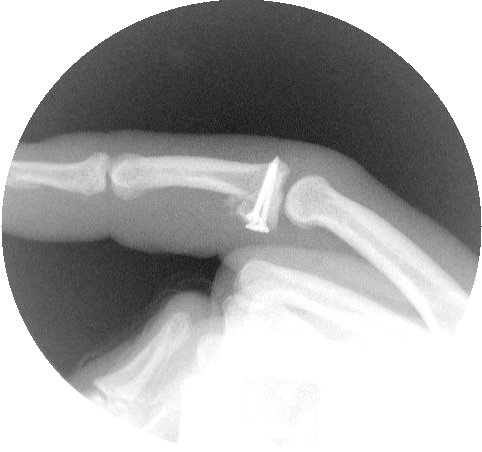

Intraoperative fluoroscopy confirms proper realignment of the joint with the bone graft in place.

The pins are replaced with screws, one at a time. Here, two 1.3mm and one 1.0mm screws were used.